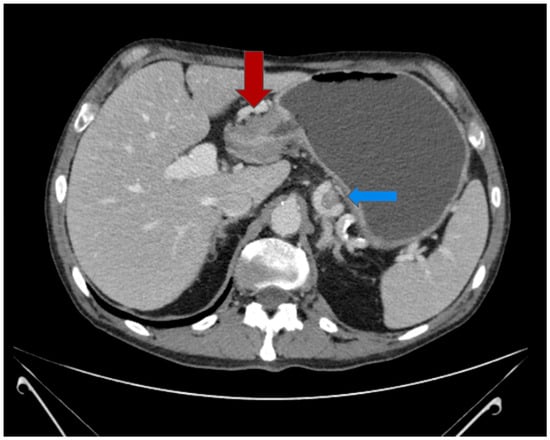

2.2. Multimodal Approach and Treatment

2.3. Postoperative Course